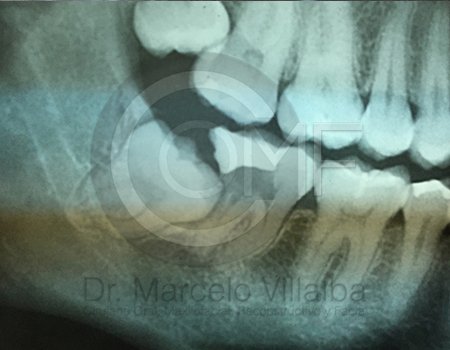

Antes de la extracción se realiza una valoración clínica y estudios de imagen, como radiografías panorámicas o tomografías, para conocer la posición del tercer molar, su relación con los nervios y planificar un procedimiento seguro y adecuado para cada paciente.

No es recomendable. Antes de extraer terceros molares es necesario realizar una valoración clínica y estudios de imagen para conocer la posición del diente, su relación con los nervios y el tipo de procedimiento más seguro para cada paciente.

Algunas extracciones simples de otras piezas dentales pueden ser realizadas por un odontólogo general; sin embargo, por la complejidad que presentan los terceros molares, o si se encuentran retenidos, impactados o cerca de estructuras importantes, se recomienda que el procedimiento sea realizado por un cirujano maxilofacial para mayor seguridad y control del tratamiento.